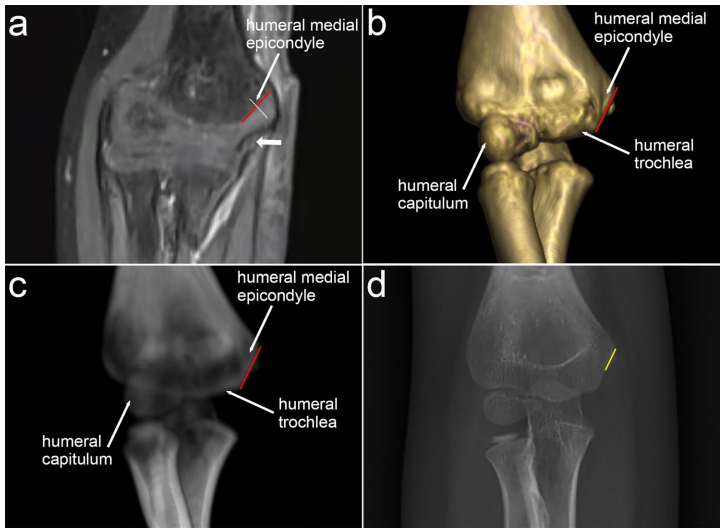

【Identification of a safe medial pinning zone based on reconstructed elbow images】章节揭示:MRI清晰显示尺神经走行于斜线下段沟槽内(图1a),3D-CT重建证实上段斜线区域无神经干扰(图1b)。侧位视图中,无论C臂机如何倾斜,由冠突窝与鹰嘴窝皮质汇聚形成的钻石形结构始终存在(图2),这个被命名为"钻石区"(diamond zone)的区域与尺神经解剖位置保持安全距离。